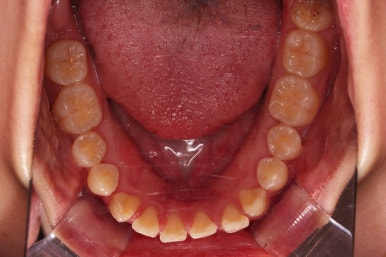

초진 시 입안의 모습입니다.

치열이 많이 삐뚠 것은 아니지만 앞니쪽이 삐뚤어 있고요. 아랫니 사이사이에 고루 틈새가 있네요.

윗니는 삐뚤고(공간부족), 아랫니는 틈새가 있다면(공간 과잉) 그 부조화는 부정교합을 의미합니다.

어금니 교합이 전반적으로 아랫니가 뒤로 빠져있는 교합이어서 맞물림이 좋지 못한 상태였어요.